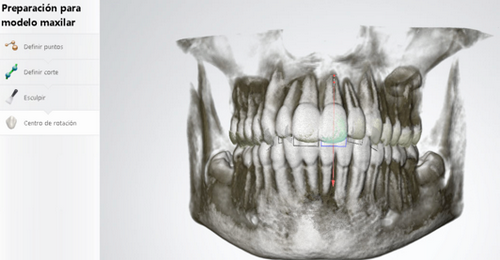

La información a la que nos estamos refiriendo la vamos a explicar punto por punto a continuación. En primer lugar, hablaremos de nuestra última incorporación en el diagnóstico que es el Escáner 3D. Es cuestión de sólo 10 minutos el poder reproducir, diente a diente, la boca de un paciente, en una pantalla a tiempo real, a todo color y con una gran calidad de la imagen. Podemos apreciar si el paciente tiene alguna pieza dental rayada, alguna parte descascarillada. Con esta prueba obtenemos el volumen y el estado de todas las piezas dentales de la arcada superior e inferior y también de cómo muerde el paciente, información clave para saber si sus dientes encajan bien o no.

Los casos quirúrgicos son aquellos en que los huesos no están coordinados. Pueden ser por inclinaciones anómalas de los maxilares como la mordida abierta o porque lo maxilares son de distintos tamaños, demasiado grande o pequeña. El cirujano tiene que colocar el hueso en la posición correcta y el ortodoncista debe colocar los dientes en posición correcta dentro del hueso para la coordinación óptima de los huesos. Para ello, a lo largo del tratamiento, se deben tomar medidas de la boca cada 2 ó 3 meses. Estas medidas se hacen con la pasta de alginato, que para algunos pacientes son una auténtica incomodidad porque les da mucha angustia. Este sufrimiento se ha acabado con el Escaner 3D. Con esta nueva tecnología podemos ir analizando cómo evoluciona la boca del paciente, que en los casos quirúrgicos se va desencajando poco a poco, con todos los datos, de las tomas iniciales, intermedias y finales, para comprobar que estás avanzando en el objetivo a alcanzar.

También con el Set Up podemos analizar qué movimientos se van a producir en los dientes del paciente hasta conseguir un engranaje perfecto para su boca. Permite ver los movimientos ortodóncicos de forma virtual, así cogemos los dientes los colocamos les damos la información del movimiento que queremos y podemos ver si van a caber o no dentro del hueso, de si van a permitir una función correcta. Con esto respondemos a preguntas fundamentales como: ¿Necesidades de espacio: expansión? ¿Tipo de anclaje: dental u óseo? ¿Necesidades de stripping(limado de dientes) o extracciones? y la pregunta más importante qué tipo de aparato de ortodoncia va a ser el mas adecuado para ese proceso.